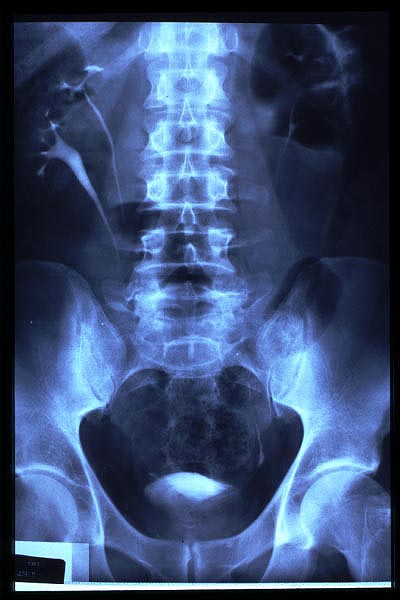

Escoliosis. Espondilolistesis.

Artrosis lumbar con pinzamiento.

Artrosis lumbar

Escoliosis, artrosis, aplastamiento...